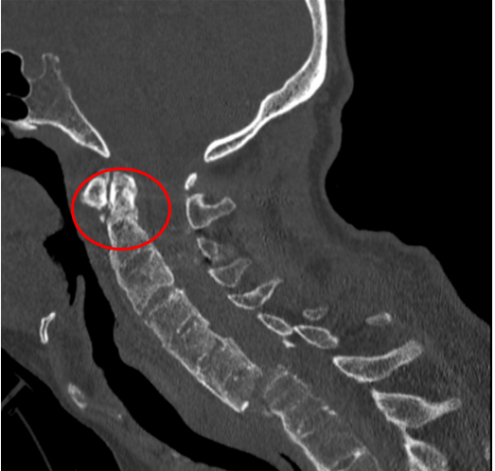

去年,家住昆山的金先生走路的时候不慎摔倒,下颌撞击硬物后感到颈部疼痛难忍,到当地医院查CT显示:(枢椎)齿状突骨折,骨折块向椎管方向移位。齿状突骨折属于上颈椎,位于头颅和颈椎的交界区域,是连接生命中枢的要塞,解剖结构复杂,有椎动脉和中枢神经从中穿过,稍有不慎就会引起大出血、瘫痪、甚至立即死亡。这类手术属于上颈椎手术,曾一度被视为骨科的手术禁区,国内仅有少数医院能够开展这一类手术,一般医师不敢轻易尝试。在业内医师的推荐下,家属送金先生来到了苏州大学附属独墅湖医院,找到了姜为民主任。

接诊后得知,金先生还患有强直性脊柱炎多年,这种疾病直接的后果是脊柱强直如棍棒,骨质变脆易骨折,被冠名以“不死的癌症”。姜主任详细了解金先生的病史后,认为该患者的治疗关键在于以下三个方面:一是脊柱强直,手术部位的位置深难以显露,解剖复杂。二是C2、C3左侧椎弓根发育异常狭小,置入椎弓根螺钉困难。三是齿状突骨折向后方移位明显,通常向前脱位较为常见复位也较容易,此种脱位的复位具有较大的难度和损伤脊髓的风险,对于术者而言是个巨大考验。

金先生伤后第7天,姜主任医师团队在麻醉手术科的密切配合下成功为他实施手术。姜主任凭借多年徒手置钉的过硬技术经验,2小时不到便完成了手术,术中出血仅100ml。术后CT显示齿状突完美复位,螺钉“不偏不倚”的位置恰到好处。术后,金先生在骨科护士长张霞芬护理团队的精心护理下,15天后伤口拆线康复出院。